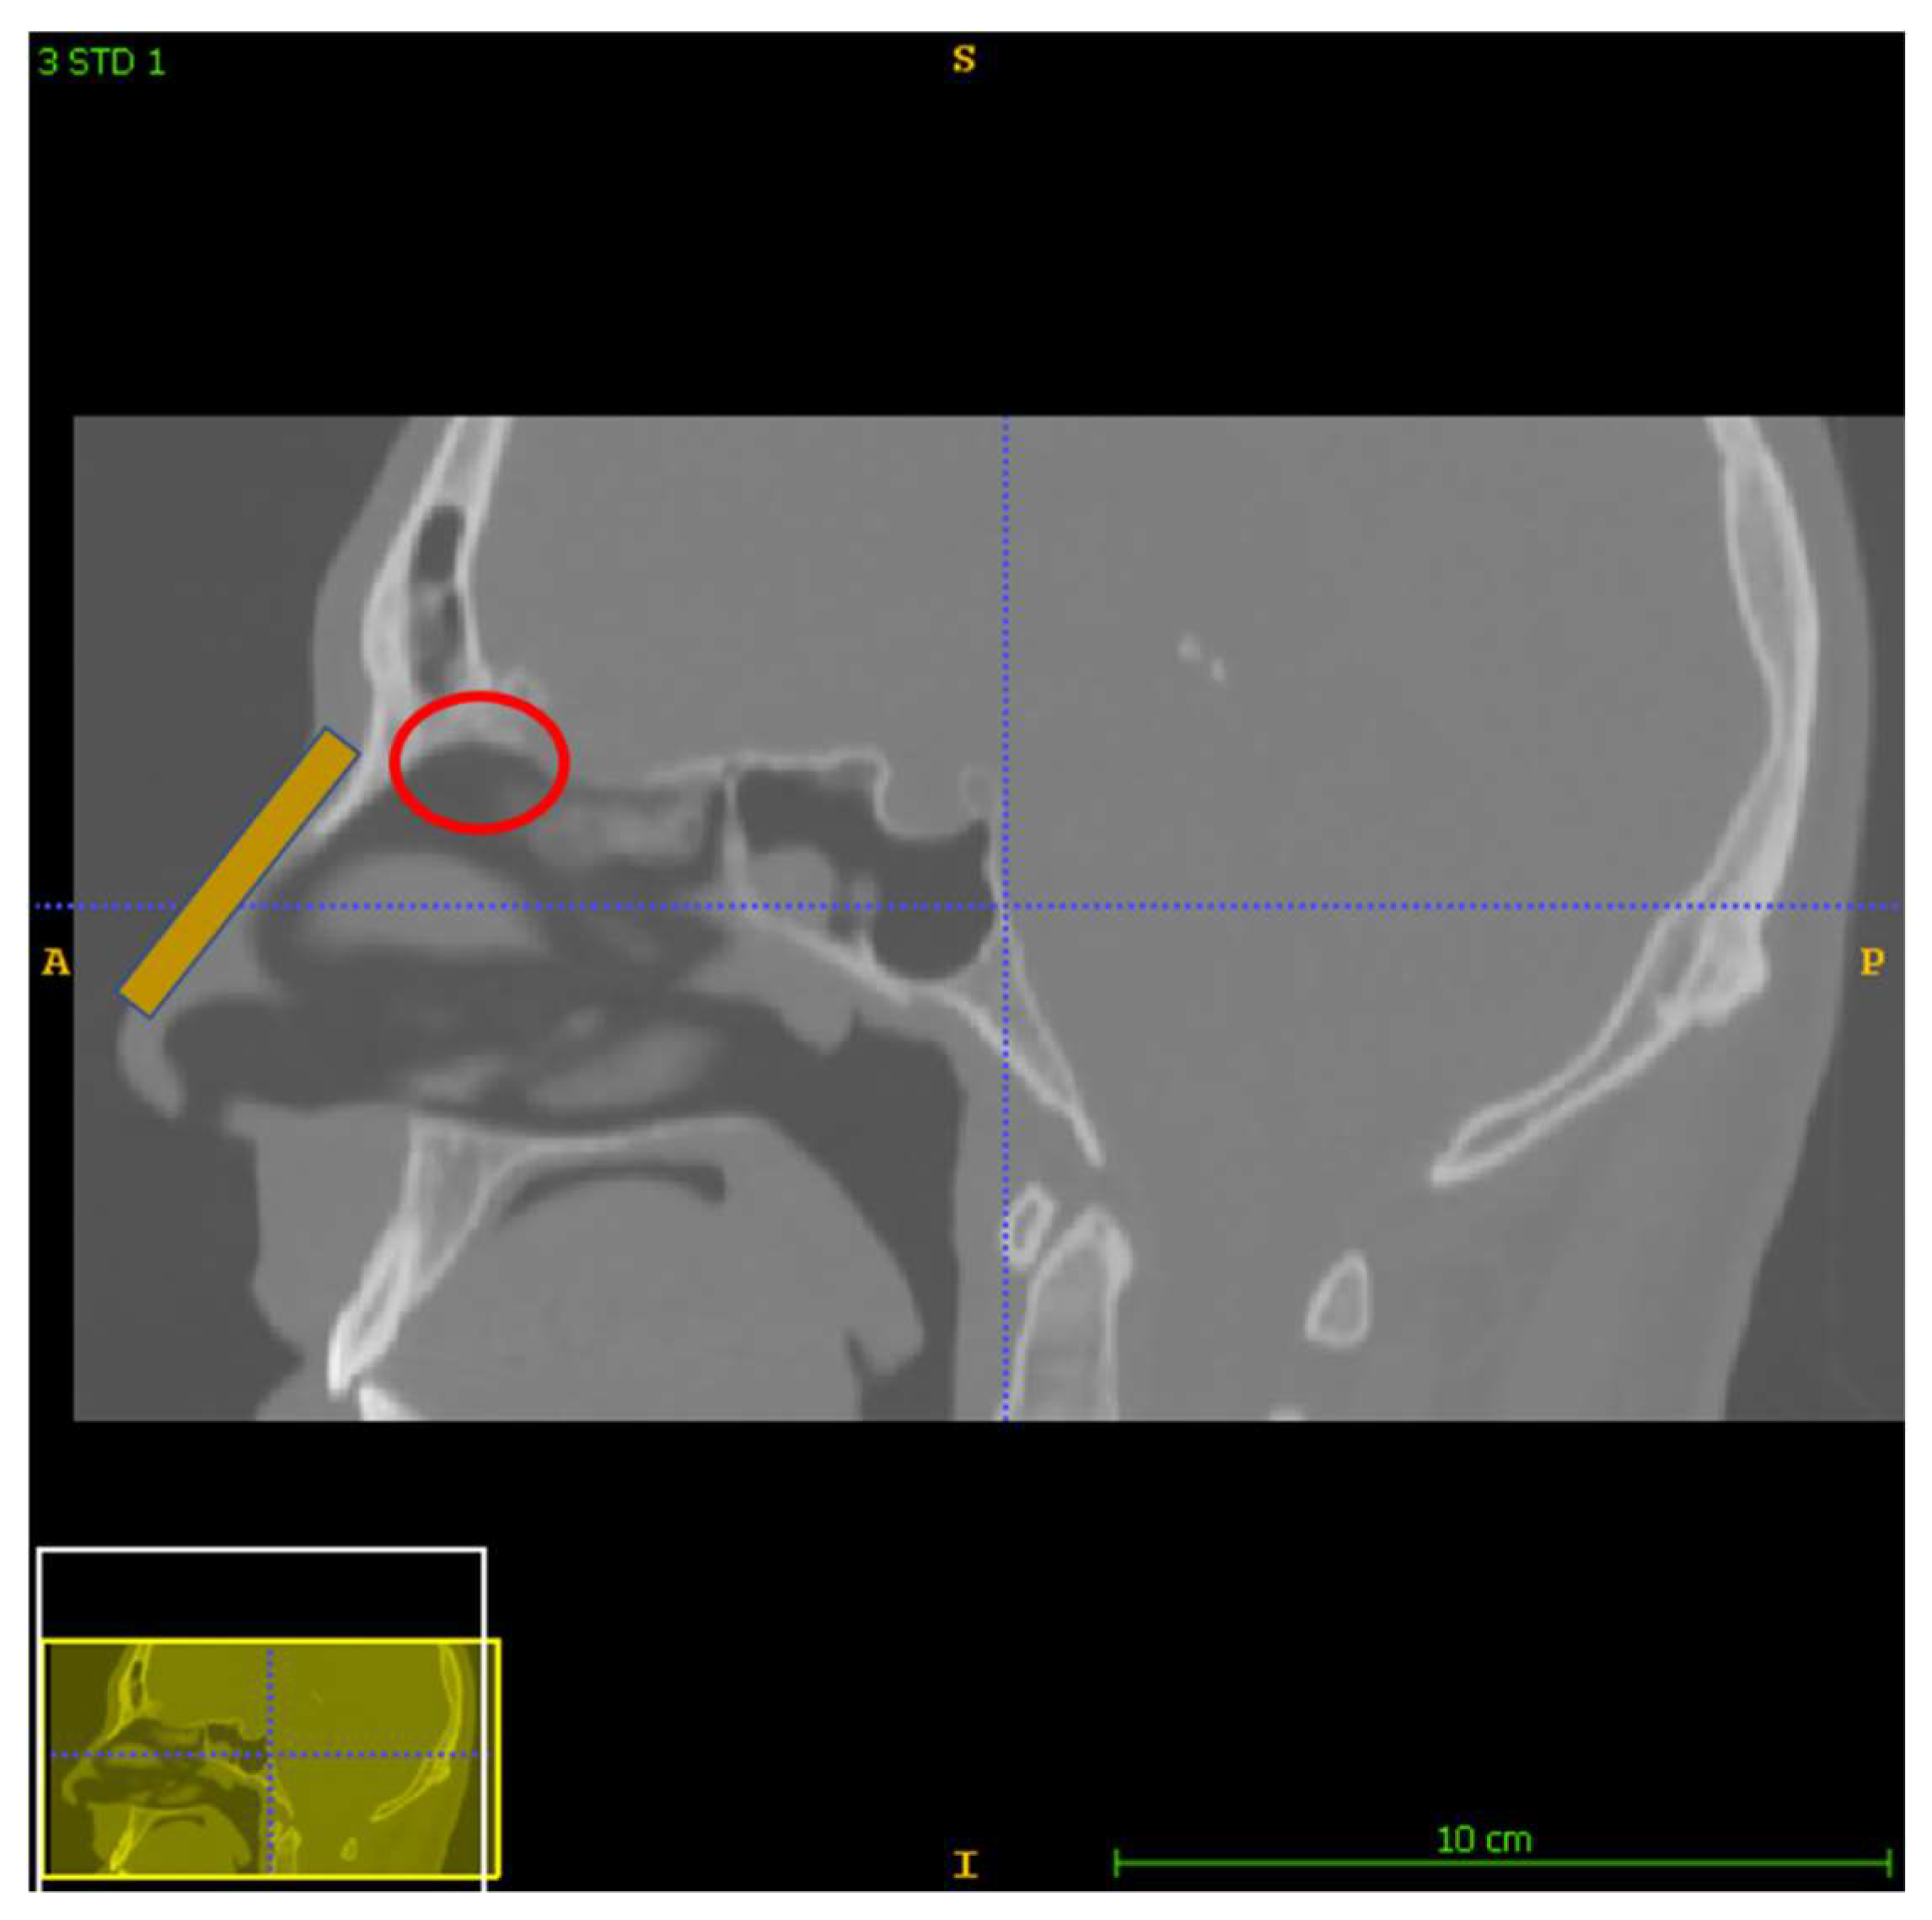

This section offers a detailed presentation of the materials and the methods implemented in the analysis. More specifically, the nose model construction, as well as the protocols of this study are described, along with the software and numerical details of the analysis. Lastly, the parametrized analysis is outlined, including the fluid dynamics, the magnetostatic and the particle tracing approaches. In this study, three different delivery approaches were analyzed based on a layout of two permanent neodymium-iron-boron (NdFeB) magnets (with a remanence of 1.2 T) placed on the nasal septum (Figure 1). The geometry was reconstructed from a real CT head image. For all protocols, the delivery efficiency was calculated on the olfactory region as the percentage of particles reaching the olfactory region of the total number of particles released in the nose.

Since the areas of interest were the nose and the nasopharynx, the software ITK-SNAP was used to extract them [20]. The segmentation was performed semi-automatically by intervening in every CT slice in order to make sure that the resulting model was as detailed as possible. Figure 2 shows in green the segmented nasal and nasopharyngeal volumes. The sinuses were not included in the model, since they were not included in the analysis (see Section 2.2 below). The final model geometry contained 238,460 facets and was exported in STL format.

It is clear from the paths shown in Table 1 that the delivery efficiency is 2% for Protocol 3 and 0% for the other two protocols, since no particle is located on the olfactory region for the last two protocols (Figure 1, red circle). The results from the first protocol indicate that all the microparticles are collected in the front part of the nasal valve region, because the field gradient is larger there, close to the edge of magnet 1. Protocol 2 shows a similar behavior. There are no microparticles collected close to the olfactory region. Instead, there is a high concentration of particles on the lateral wall, just above the internal nasal valve. In contrast, Protocol 3 achieves an efficiency of 2% because it differs from the other two protocols in terms of its magnitude, the direction of its magnetic flux and its gradient.

Figure 1. The general layout of the protocols analyzed. A permanent magnet is placed on the nasal septum (orange). The red circle indicates the olfactory region which occupies about 8% of the total nasal passage surface.